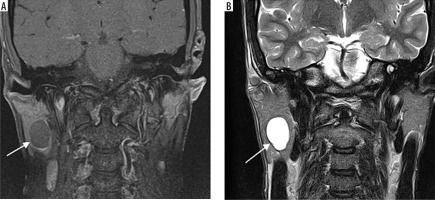

Case 1: Parotid lymphoepithelial cyst

A 30-year-old male patient presented with painless swelling of the right parotid region. Coronal section of MRI shows a right parotid lymphoepithelial cyst. Cystic lesion with water content has low signal intensity on T1-weighted images, hence appears hypointense. In contrast, it has high signal intensity on T2-weighted images and has hyperintense appearance (Figures 4A-C).

Figure 4

Coronal section of MRI of parotid lymphoepithelial cyst. A) T1-weighted MRI image – note the hypointensity of the cyst on right parotid gland. B) T2-weighted MRI image – note the hyperintensity of the cyst. This classic signal pattern helps differentiate cystic lesions from other tumours, highlighting the importance of correlating imaging features with the clinical context for accurate diagnosis and treatment planning [Courtesy: Radiopaedia. DOI: https://doi.org/10.53347/rID-149218, rID:149218]

Case 2: Parotid lipoma

A 60-year-old male with painless left facial swelling. Axial MRI images of the head and neck region, showing a lesion in the left masticator space; well-defined lobulated mass of the left parotid gland. On MRI, because lipoma is composed of mature fat, it typically appears hyperintense on both T1-weighted and T2-weighted sequences. It closely follows the signal intensity of subcutaneous fat and will lose signal on fatsuppressed sequences (Figures 5A-B).

Figure 5

Axial section of MRI of parotid lipoma. A) T1-weighted MRI image – note the hyperintensity of the lesion on left parotid gland. B) T2-weighted MRI image – note the hyperintensity of the lesion. C) T1 C+ Fat sat – note the hypointensity of the lesion. These signal characteristics are consistent with a benign lipomatous lesion, which aids in preoperative differentiation from other malignant parotid tumours [Courtesy: Radiopaedia. DOI: https://doi.org/10.53347/rID-184951, rID: 184951]